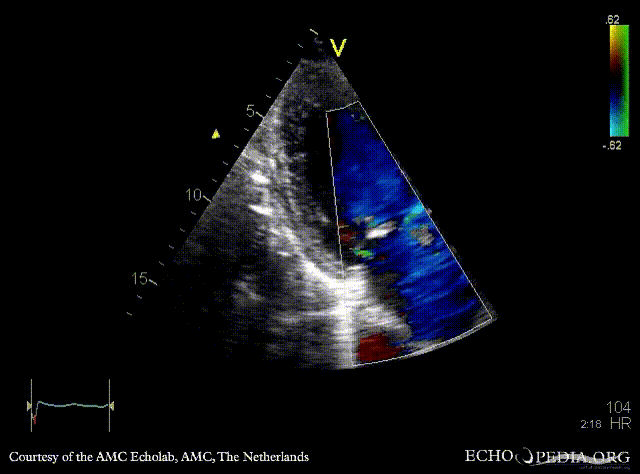

Endocarditis of mitral valve

A3CH: vegetations on AMVL A2CH

A5CH A5CH: Color doppler, severe mitral regurgitation